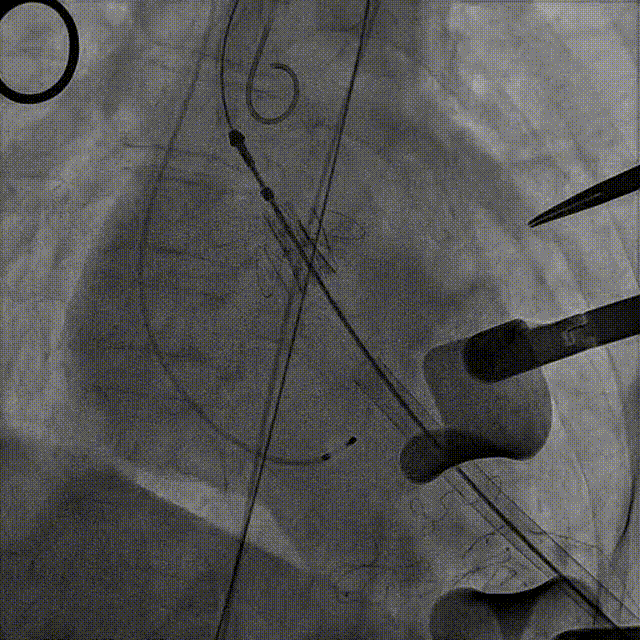

近日,中国人民解放军南部战区总医院王显悦教授、张本教授团队应用J-VALVE瓣膜完成一例高难度经心尖TAVI。患者为72岁男性,心脏超声示主动脉瓣重度狭窄伴轻度关闭不全,且二尖瓣中度狭窄。由于具有急性心力衰竭、高血压3级、肺气肿等其他疾病,且体重仅35公斤,对外科开胸手术耐受较差,风险极大,经过团队综合评估,决定行经心尖TAVI手术,拟植入25mm J-VALVE瓣膜。该患者存在升主动脉瓷化和左室流出道重度钙化,为手术增加了额外难度,术者团队凭借过硬的专业技能和细节处理能力,有效避免了术中可能存在的风险,并成功植入瓣膜。术后食道超声示无瓣周漏、无冠脉堵塞等并发症,患者症状明显缓解,手术顺利完成。

该患者升主动脉瓷化,左室流出道重度钙化。在TAVI手术过程中,导管和瓣膜的通过可能会对瓷化主动脉造成损伤,增加主动脉夹层、血管破裂等严重并发症风险;左室流出道的重度钙化会影响人工瓣膜与周围组织的贴合,使得瓣膜无法完全密封,从而增加瓣周漏的发生概率。

手术过程